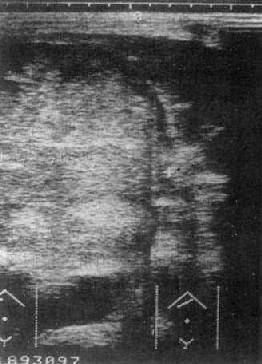

原发性肝癌:USG是影像学诊断中的首选方法。声像图上肝癌表现为聚集成团的强回声区,光团强弱分布不均,边比缘不规则。光点常粗糙明亮,与正常肝组织有明显差别。肿瘤区下方的正常肝组织回声强度降低,系因肝癌引起的超声衰减所致(图4-3-2)。

图4-3-2 肝癌(巨块型)